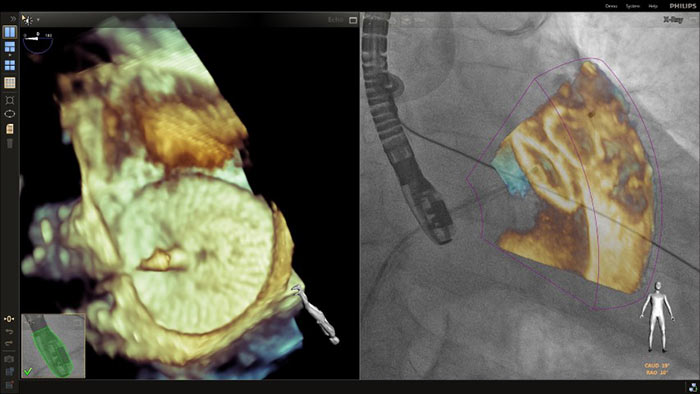

En el centro de nuestra suite, la exclusiva solución EchoNavigator es el ejemplo emblemático del compromiso de Philips con la multimodalidad y la integración del flujo de trabajo, aporta lo mejor de ambos mundos del líder de la industria en soluciones cardíacas intervencionistas de rayos X y ecografía.

Segmentación del modelo EchoNavigator 3D

Dimensionamiento de la TAVR totalmente automatizado con HeartNavigator

Optimización de la vista de la válvula mitral con modelos de corazón EchoNavigator

Visualización de las válvulas mitral y aórtica con modelos cardíacos EchoNavigator